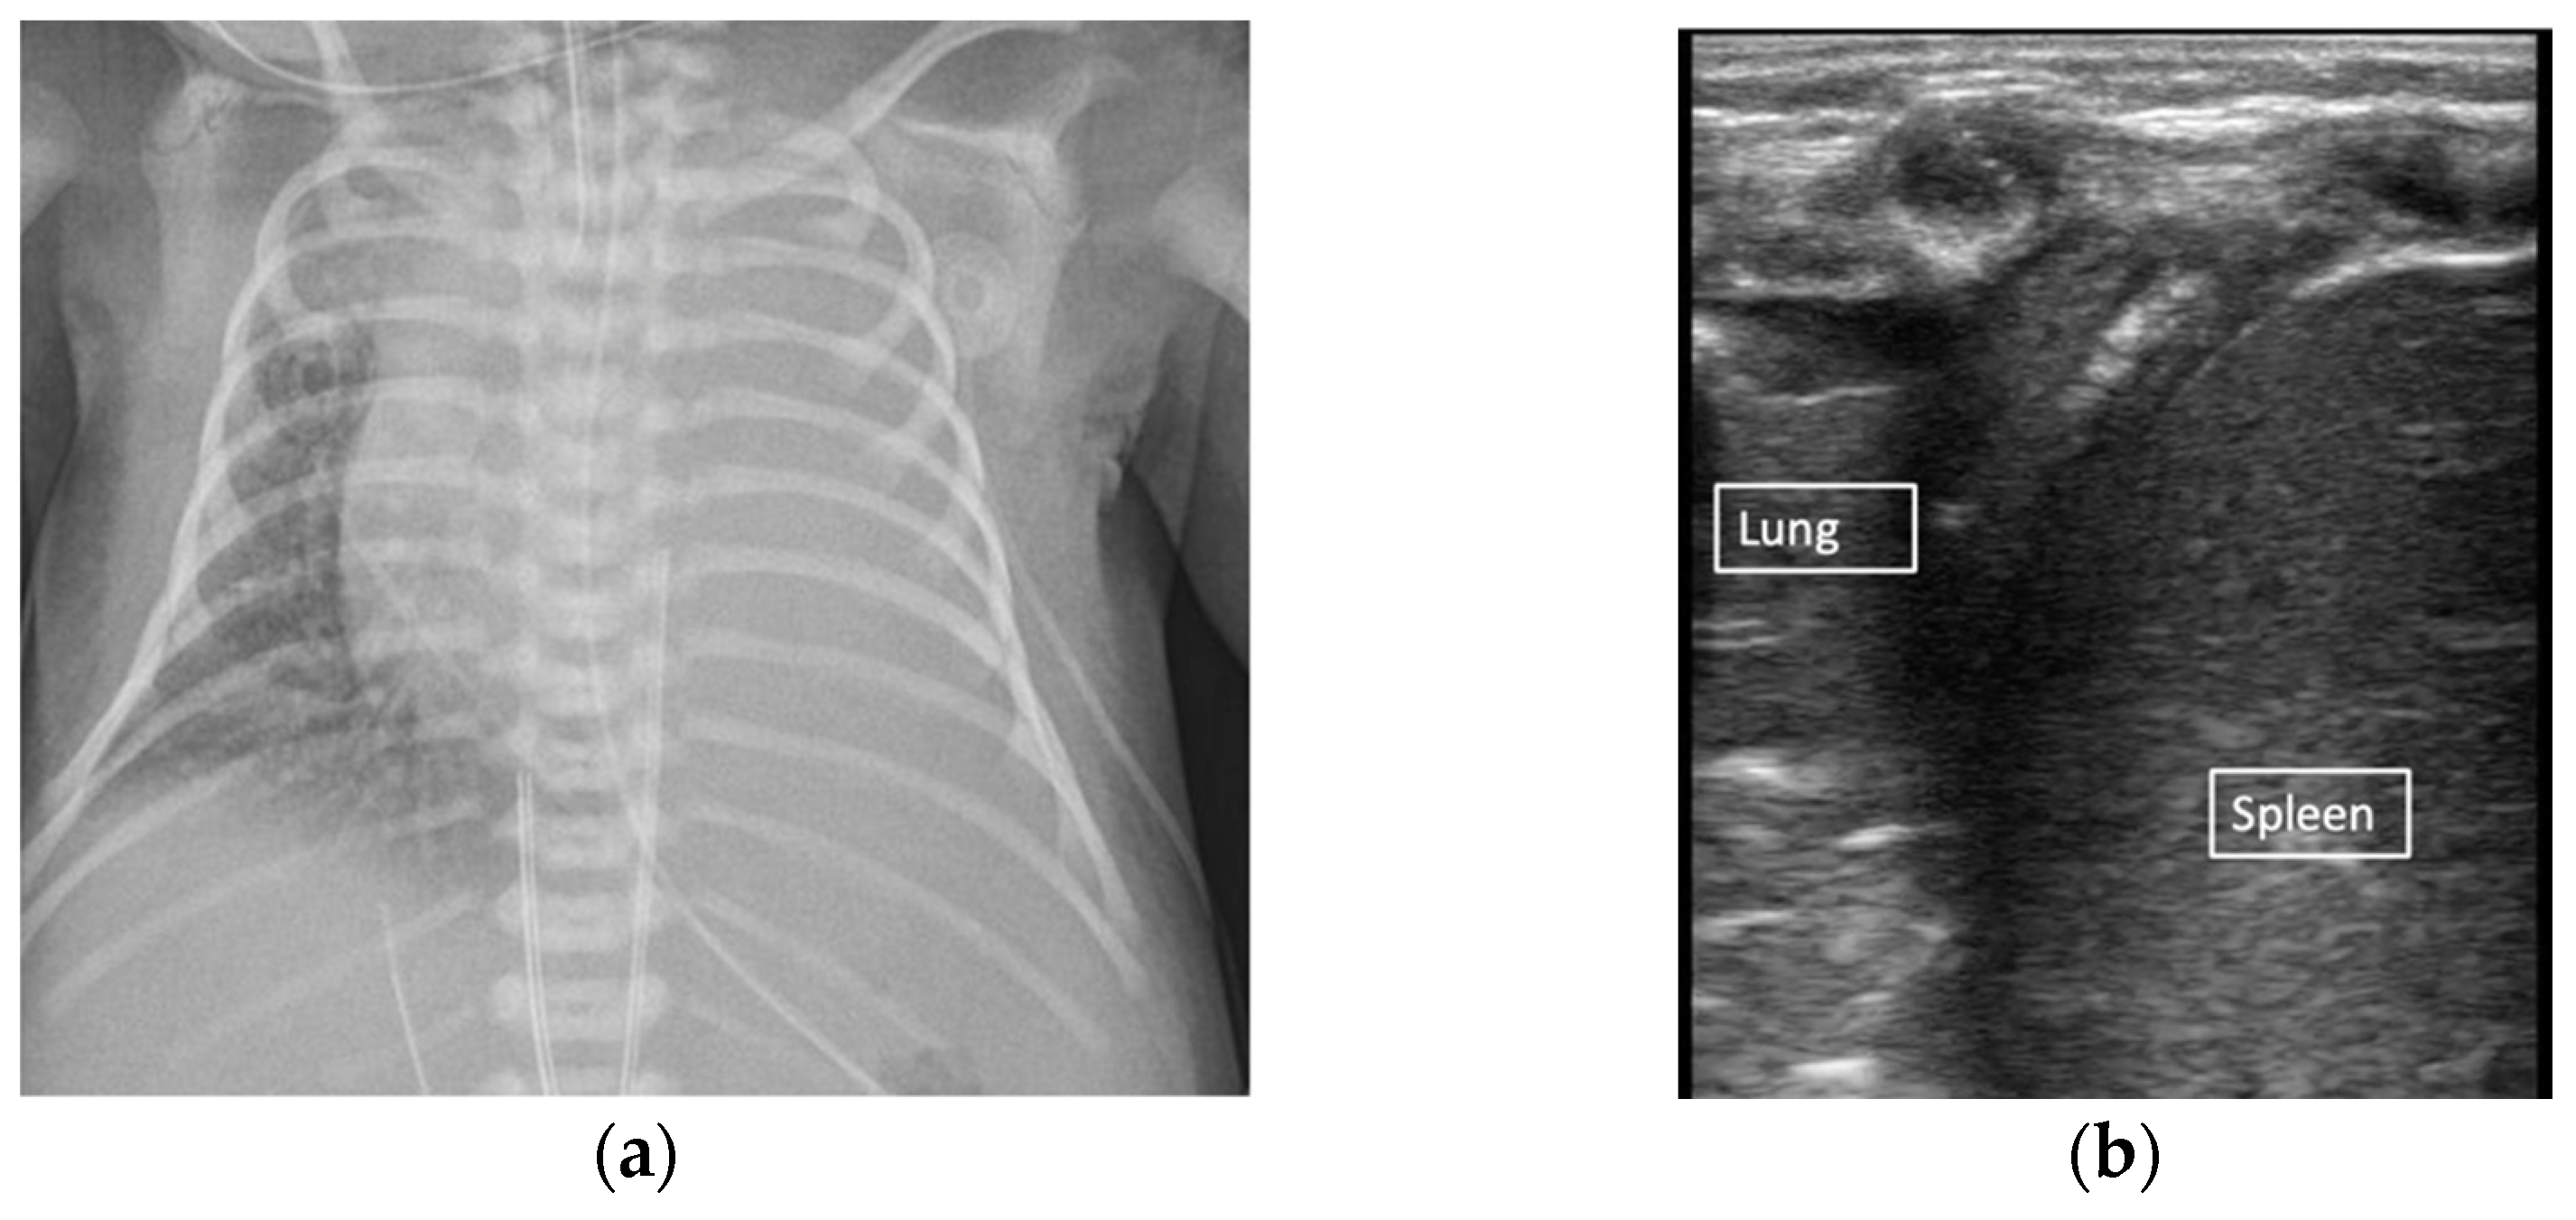

Figure 5. Effusion vs complete atelectasis. Large effusion suspected on chest X-ray (a). B-mode demonstrating complete atelectasis of the left lung without large pleural effusion (b).

Atelectasis is demonstrated as a consolidation with the anechoic border and a disruption of A-lines [8,31]. Complete atelectasis can cause an absence of lung sliding and hepatization of the lung on ultrasound [1,31]. Lung pulse can also be observed in severe atelectasis, where the atelectatic lung appears to be pulsating with the beats of the heart [31]. Atelectasis can present as static air bronchograms in early stages vs. pneumonia, which is demonstrated as dynamic air bronchograms that move with respiration [32,33]. In clinical practice, it is difficult to discern static vs. dynamic air bronchograms, making the diagnosis of atelectasis vs. pneumonia a continued challenge. Complete atelectasis vs. pleural effusion can be difficult to distinguish on a chest X-ray, but can be easily identified on LUS in real time (Figure 5, Supplementary Materials Video 3).